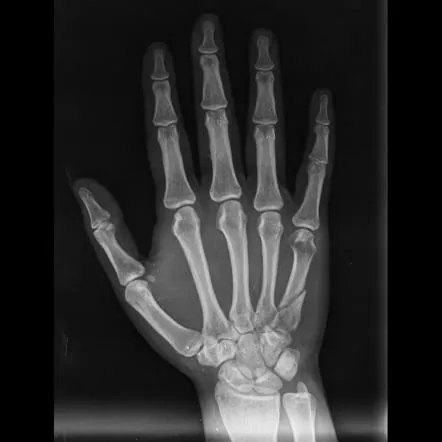

Frakturen der Mittelhandknochen, der langen Knochen der Hand, die die Finger mit dem Handgelenk verbinden, sind häufige Verletzungen, die oft durch Stürze, sportliche Aktivitäten oder direkte Traumata verursacht werden. In den letzten Jahren haben bedeutende Fortschritte in der Medizintechnik zur Entwicklung von Mittelhandknochen-Verriegelungsplatten geführt und damit die Behandlung von Handfrakturen revolutioniert. Diese innovativen Implantate haben sich bewährt

Mittelhandfrakturen können in Schwere und Lage unterschiedlich sein und verschiedene Teile der Hand betreffen. Sie werden üblicherweise in verschiedene Typen eingeteilt, darunter:

Mittelhandknochen-Verriegelungsplatten stellen einen großen Durchbruch bei der Behandlung von Handfrakturen dar. Diese Platten wurden speziell entwickelt, um eine stabile Fixierung und Unterstützung während des Heilungsprozesses zu gewährleisten.